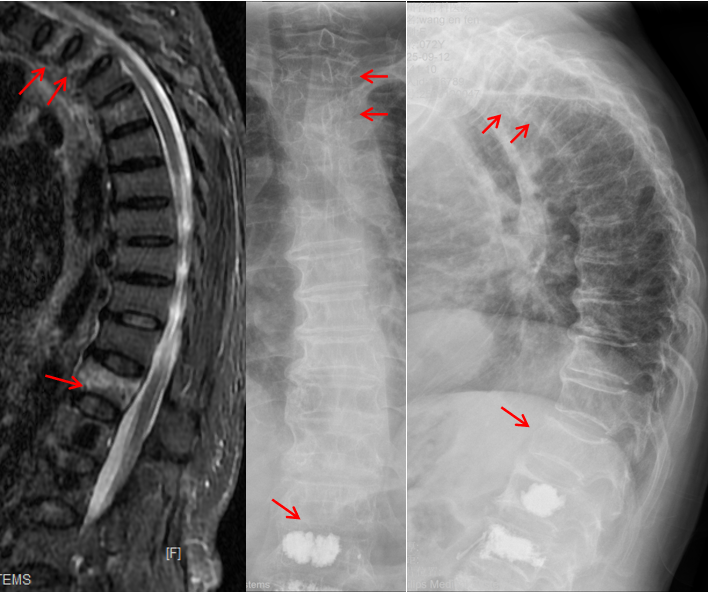

王阿姨的病情,从一开始就牵动着所有人的心。摔倒后,她随即出现胸部、肩背及腰部的剧烈疼痛,哪怕轻微咳嗽、翻身,疼痛都会急剧加剧,甚至连正常呼吸都变得困难。家人紧急将她送往北京积水潭医院贵州医院,经胸腰椎X线与核磁共振检查后,确诊其为胸2、胸3及胸12多发胸腰椎椎体压缩性骨折(图1),其中胸2、3、12椎体骨髓水肿明显,为导致她此次疼痛的“罪魁祸首”。